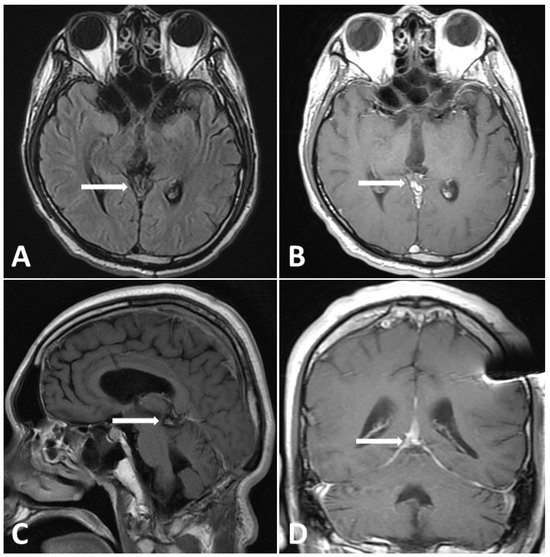

MRI performed 3 months after chemotherapy showed complete remission of the pineal germinoma as shown in Figure 5. The patient’s neurological function recovered well. Twelve months after chemotherapy, at outpatient follow-up, MRI demonstrated no tumor relapse, accompanied by β-HCG and AFP levels within the normal range (Figure 6). The patient was completely independent and actively participated in military career.

Figure 5.

Follow-up MRI (3 months post treatment). (A) T2-FLAIR images showing evidence shrinkage of lesion without perifocal edema. (B–D) Gadolinium-enhanced MRI, revealing dramatic shrinkage of previous pineal tumor.